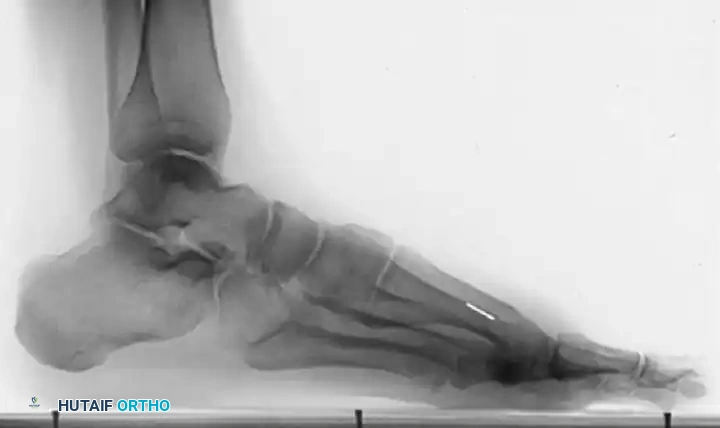

Patient with stage II hallux rigidus

Figure 1: Patient with stage II (radiographically) hallux rigidus; note the prominent dorsal osteophyte over the first metatarsal.